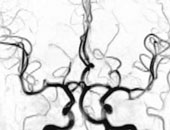

Venen

Florian Kronenberg und seine Mitarbeiter vom Institut für Medizinische Biologie und Humangenetik der Uni Innsbruck haben nun in einem vom FWF unterstütztem Projekt einen Zusammenhang zwischen niedrigen ApoA-IV Konzentrationen und koronaren Gefäßerkrankungen beim Menschen nachgewiesen. Ein zu hoher Cholesterinspiegel im Blut fördert die Entstehung von Arteriosklerose. Mangelnde Bewegung, hoher Nikotinkonsum und übermäßige Nahrungsaufnahme sind die äußeren Gründe für die Fettstoff-Wechselprobleme, die zur Ablagerung von Cholesterin in den Blutgefäßwänden führen. Diese Zusammenhänge sind bekannt und in der medizinischen Praxis berücksichtigt. Relativ neu allerdings sind Hinweise, dass das ApoA-IV antiatherogene Eigenschaften hat und sich damit positiv gegen die degenerativen Veränderungen der Gefäßwände bei Arteriosklerose auswirkt. ApoA-IV ist an mehreren Schritten des Cholesterin-Rücktransportes beteiligt, der Cholesterin zur Leber oder anderen Organen transportiert, in denen es verarbeitet wird. Darüber hinaus ließ sich bei Mäusen mit einem überdurchschnittlich hohen ApoA-IV Spiegel eine deutlich verminderte Entwicklung von Arteriosklerose nachweisen. Nach der Kreuzung mit Mäusen, die aus genetischen Gründen eine starke Arteriosklerose aufweisen, kam es zu einer deutlichen Verbesserung des Arteriosklerose-Ausmaßes in der nächsten Generation. "Grund genug, dieses Protein näher zu studieren. Dabei müssen zunächst jene Variablen festgestellt werden, die einen Einfluss auf die ApoA-IV Konzentration haben", so Kronenberg.

Um diese Einflussfaktoren zu erfassen, hat Kronenberg im Rahmen der "Bruneck-Studie" den ApoA-IV Spiegel von rund 1000 Personen gemessen und die Ergebnisse in Beziehung zu ausführlichen Informationen zu Diät, Trainingszustand und Laborparametern gestellt. So konnten sowohl Einflussvariablen als auch das Ausmaß der Beeinflussung ermittelt werden. Kronenberg: "Wir konnten zeigen, dass die Konzentrationen von ApoA-IV z.B. durch Nierenerkrankungen massiv ansteigen. Daher können hohe ApoA-IV Spiegel ein früher Parameter für die Diagnose von Nierenkrankheiten sein." Kronenberg will auch feststellen, ob ApoA-IV bei der Entstehung und dem Fortschreiten der Arteriosklerose tatsächlich eine direkte Rolle spielt. Davon hängt es ab, ob ApoA-IV als Ziel für Medikamente dienen könnte, die die ApoA-IV Konzentration erhöhen und somit das Arteriosklerose-Risiko verringern. In diesem Zusammenhang setzt Kronenberg einen Schwerpunkt auf die Frage, ob und wie die ApoA-IV Konzentrationen genetisch gesteuert sind. "Wir wollen jene Gene finden, die den ApoA-IV Spiegel beeinflussen."